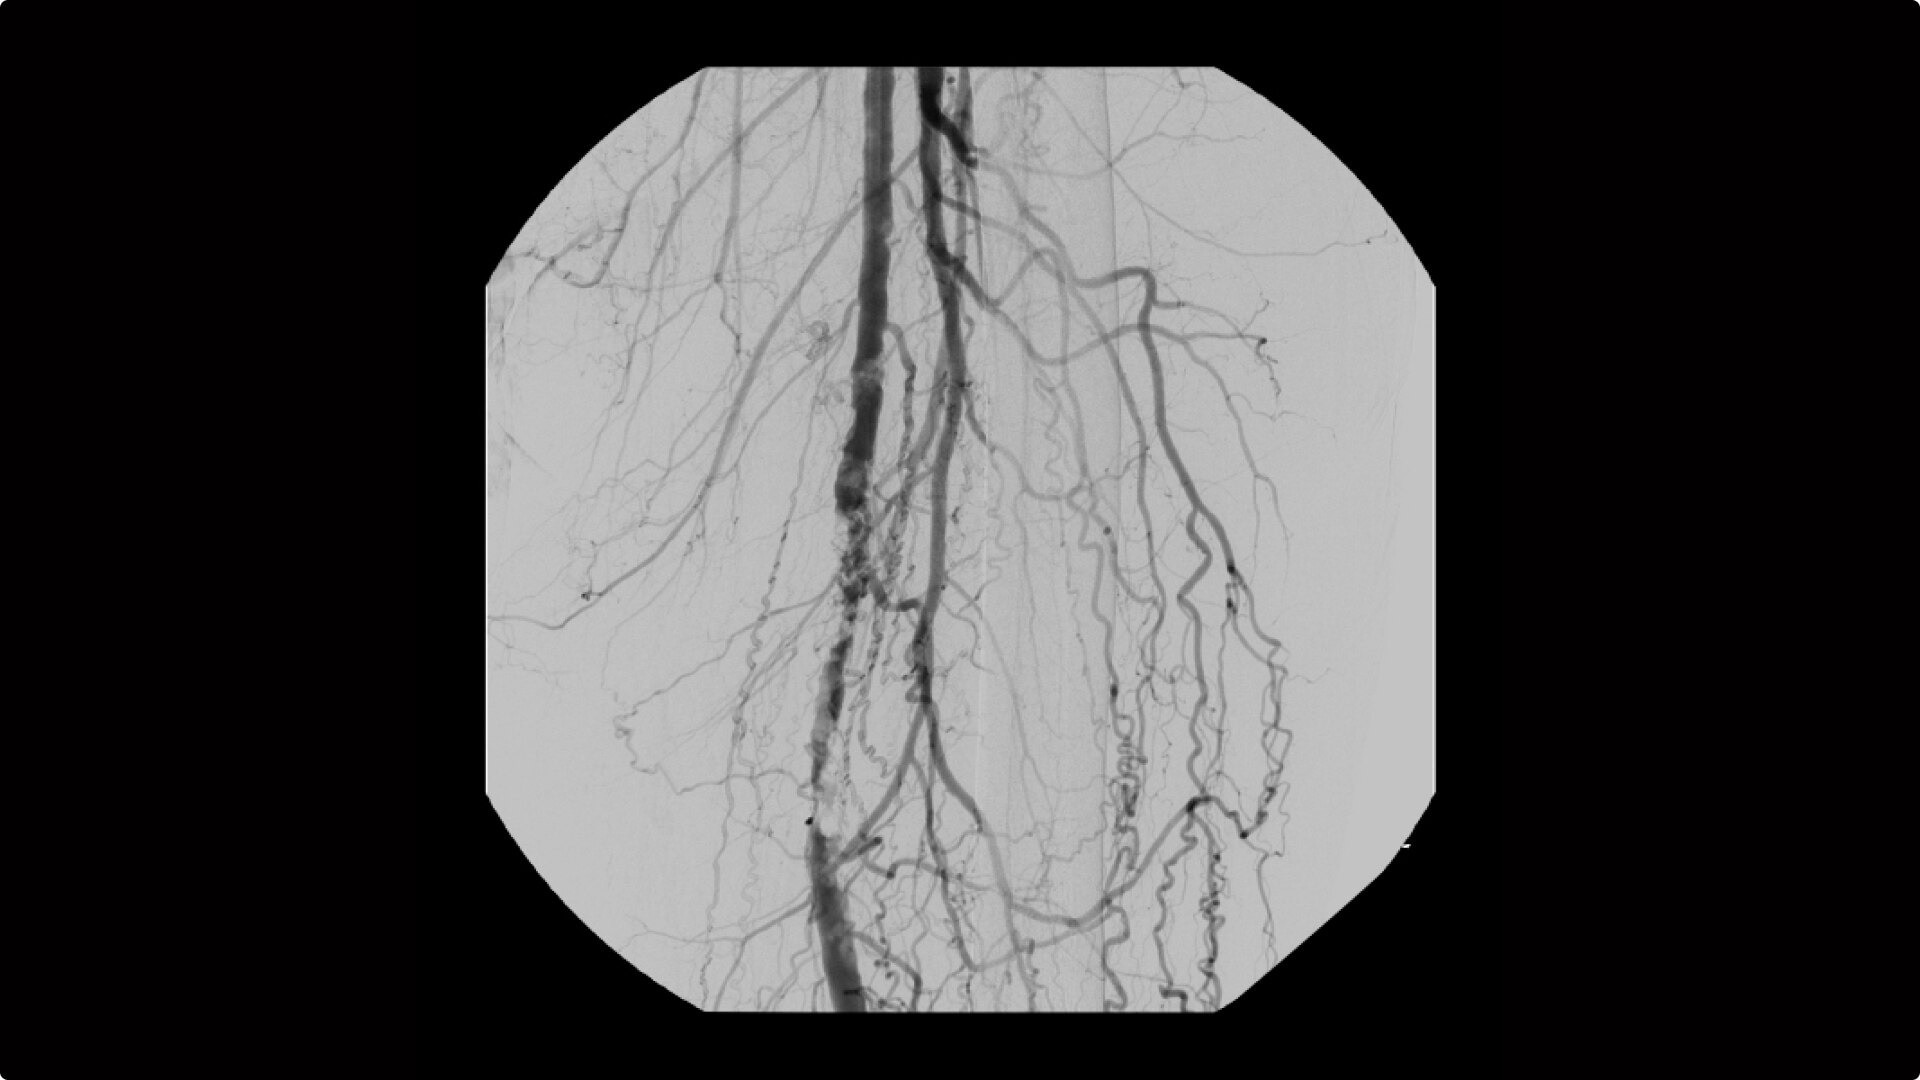

OEC C-arms are used by interventionalists and surgeons to obtain vascular imaging during peripheral to contrast run-off procedures. Superb resolution, even in the presence of motion, enables easy identification of anatomical landmarks and the extremity of the catheter, even as catheter tip moves.

Clearly see 0.014” guidewires in chest and abdomen region or 0.008” guidewires in peripheral vascular with the OEC Elite CFD with a flat detector, image processing advancements and 4K viewing display.

Experience fixed room-like images with eNR (enhanced Noise Reduction), an advanced software algorithm that automatically reduces image noise by 30% for an equivalent appearance of 30 kW power.

To see vessel stenosis or tips of guidewires, Live Zoom up to 4X during a fluoro or Cine without the additional dose of Mag modes or resulting X-ray tube heat buildup.

Conveniently plan procedures with comprehensive imaging tools to measure percent stenosis, distance, or angles, annotate and draw on images.